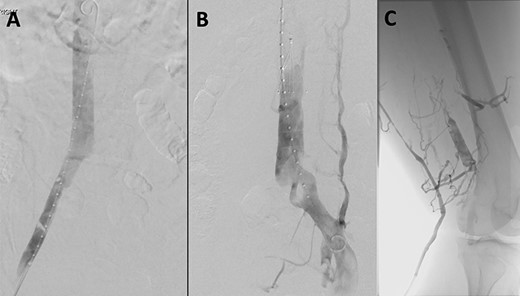

(A) Venogram illustrating patent IVC and renal vein position. (B) Post-thrombectomy venogram showing fenestrated left common iliac vein. (C) Venogram illustrating patent popliteal vein via small saphenous vein access.

After ultrasound-guided right common femoral vein access, venogram illustrated both the position of the renal veins and a patent inferior vena cava (IVC) (Fig. 2A). An infrarenal IVC filter was deployed (Celect Platinum Vena Cava Filter by COOK Medical) (Fig. 2B). A diagnostic venogram was performed via the left short saphenous vein (Fig. 2C), and this confirmed patency of the common femoral vein, femoral vein and the popliteal vein. Ultrasound was again utilized to puncture the left great saphenous vein proximally, with insertion of a 6-Fr sheath with a glide and Bern catheter used to cross the occluded common iliac vein and external iliac vein. An Angiojet thrombectomy catheter (by Boston Scientific) was placed within the thrombus, and a total of 19.4 mg of alteplase was infiltrated. After waiting 30 minutes for the alteplase to diffuse, a venogram was performed that demonstrated some resolution of the thrombus. Suction thrombectomy was then performed. Completion venogram illustrated a fenestrated left common iliac vein with resolution of the DVT (Fig. 2B). A balloon was inflated at the level of the fenestration to confirm separate channels. The irritation of the access vein’s intima for the SVT ablation in conjunction with the fenestrated common iliac vein was the suspected cause of the patient’s DVT. The patient was changed to therapeutic low-molecular-weight heparin post-operatively.